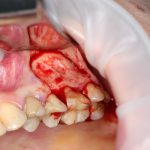

Кстати, обрати внимание на ширину альвеолярного гребня (левая картинка). Она чуть меньше 3 мм. Это объясняет, почему я засомневался в возможности установки имплантатов одновременно с остеопластикой. Понятно и без КЛКТ.

Наперво, мне нужно удалить разрушенный зуб и получить костный аутотрансплантат.

Для получения костного блока, мы открываем донорскую зону, наружную косую линию нижней челюсти.